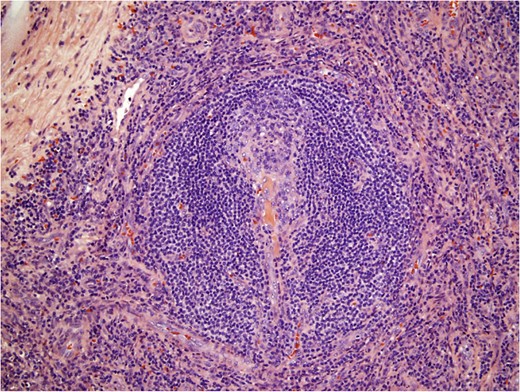

The gastrocolic ligament was opened to enter the lesser sac, exposing the mass bound by the spleen on the left, the abdominal aorta on the right, the splenic vessels and distal pancreas superiorly, and the left renal vessels inferiorly. Mobilization of the transverse colon and splenic flexure downwards and the distal pancreas and spleen upwards allowed visualization of the capsulated and well-circumscribed retroperitoneal mass (Fig. 2). The left adrenal gland was completely encased and had to be dissected en bloc alongside resection of the lesion. The mass had to be carefully detached from the splenic vessels superiorly and the renal vessels inferiorly as these structures were tenaciously attached to it. The specimen was extracted through a 5 cm periumbilical incision and sent for frozen section examination. Operative time was 140 min with minimal blood loss. The patient was discharged postoperative Day 2 without complications.

Gross pathology of Castleman’s disease arising from accessory spleen.